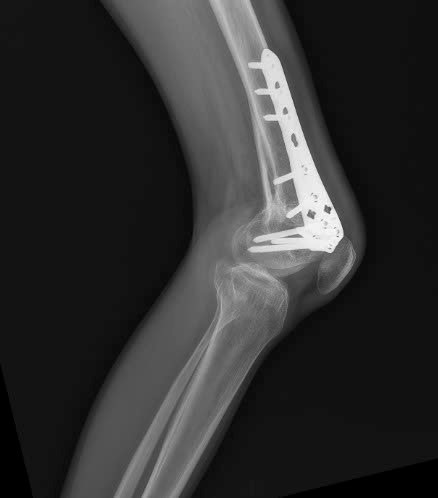

Hình ảnh Xquang sau phẫu thuật 1 năm: xương đã lành hoàn toàn, bệnh nhân có thể sinh hoạt và làm việc bình thường